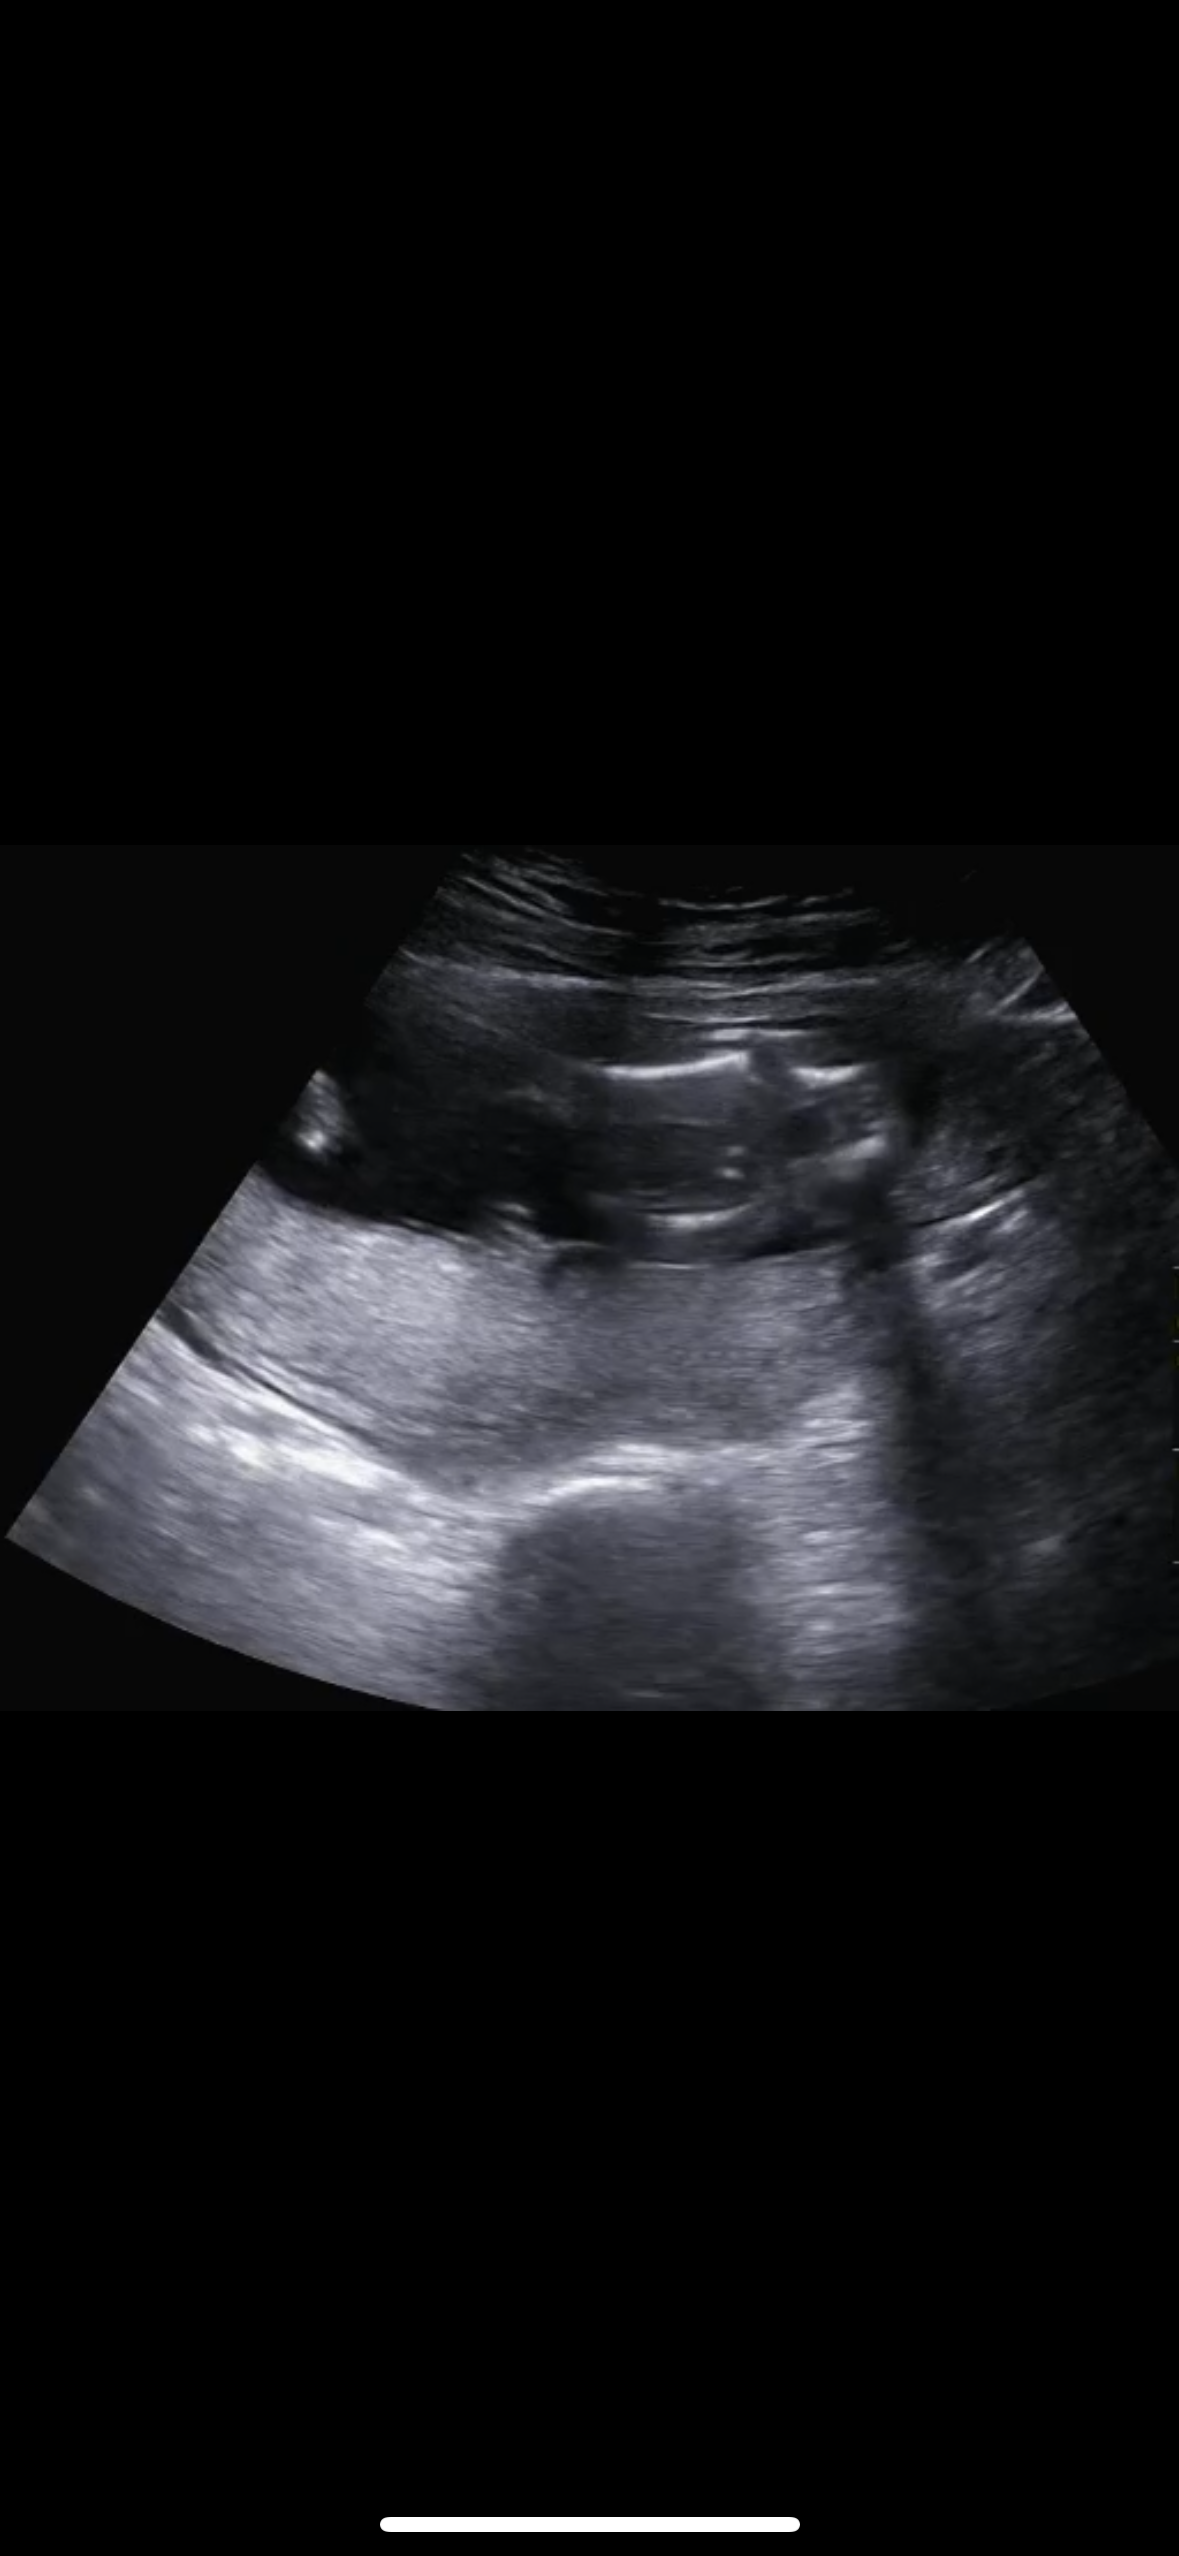

16주차 초음파인데 성별 좀 봐주세여ㅠㅠ

이 전에 올린 사진은 다리 사이를 비추었을 때 계속 보여진 부분인데 남편은 찰나에 나온 점 두 개가 계속 신경쓰이는지 이 사진으로 올려보라고 하네요ㅠㅠ 다시 한 번 도와주세요ㅠㅠ